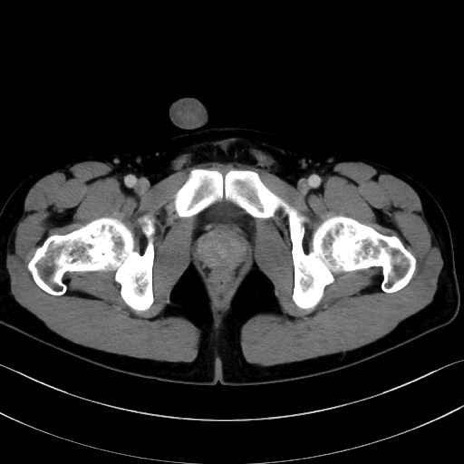

5. 大腿前面(大腿四頭筋群・伸筋群)

縫工筋 (Sartorius)

大腿直筋 (Rectus femoris)

外側広筋 (Vastus lateralis)

中間広筋 (Vastus intermedius)